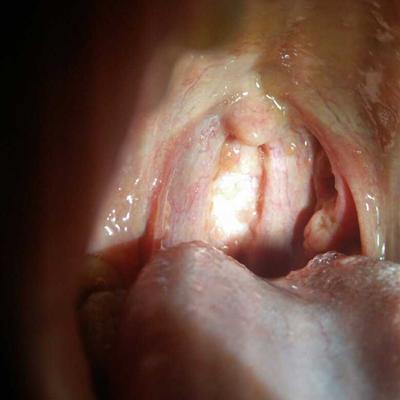

Dyspnea syndrome is characterized by dyspnea, even mouth opening and shoulder lifting, nasal instigation, and inability to lie flat. Disease treatment is mainly divided into two aspects: excess asthma in lung, deficiency asthma in lung and kidney. Subjectively, patients will feel that breathing is very laborious, and their heart is depressed. They always feel that the air around them is insufficient, and the frequency, rhythm and depth of breathing are abnormal. Face blue, lips purple, nose involuntarily incited, heart inexplicably restless. Asthma mainly occurs in asthmatic bronchitis, pulmonary infection, emphysema, cardiogenic asthma, tuberculosis and other diseases. The principle of treatment is to treat according to deficiency and excess, to treat excess asthma and lung, and to eliminate pathogenic factors and promote qi; The treatment of deficiency asthma is in lung and kidney, mainly in kidney. In short, excess asthma is in the lung, deficiency asthma is in the lung and kidney, asthma syndrome is developed from other diseases, active treatment of primary disease is the key. So how to diagnose and differentiate asthma? Now let's talk about it.

First, the etiology of asthma is always external pathogen, phlegm turbidity, emotion, deficiency of lung and kidney, etc. Asthma, exterior cold and interior heat, dyspnea, upper breath, chest distension or pain, thick breath, nasal fan, cough but not good, expectoration sticky, cold shape, body heat, boredom, body pain. Because of the lung qi deficiency, the kidney is the root of Qi. If there is something wrong with the kidney, the Qi can't return to the kidney, causing the Qi reverse to the lung and causing the asthma syndrome. Therefore, the deficiency of asthma is in the lung and kidney.

Third: how to distinguish between deficiency and excess is the key in life. Patients with excess asthma have deep and long breathing, fast exhalation, thick breath, high voice, accompanied by phlegm, cough, strong pulse, and this symptom occurs when they are young or new patients. The patients with deficiency asthma have shortness of breath, difficult to continue, rapid deep inhalation, timid breath, low voice, few phlegm cough, weak pulse, and the elderly or long sick often have deficiency syndrome.